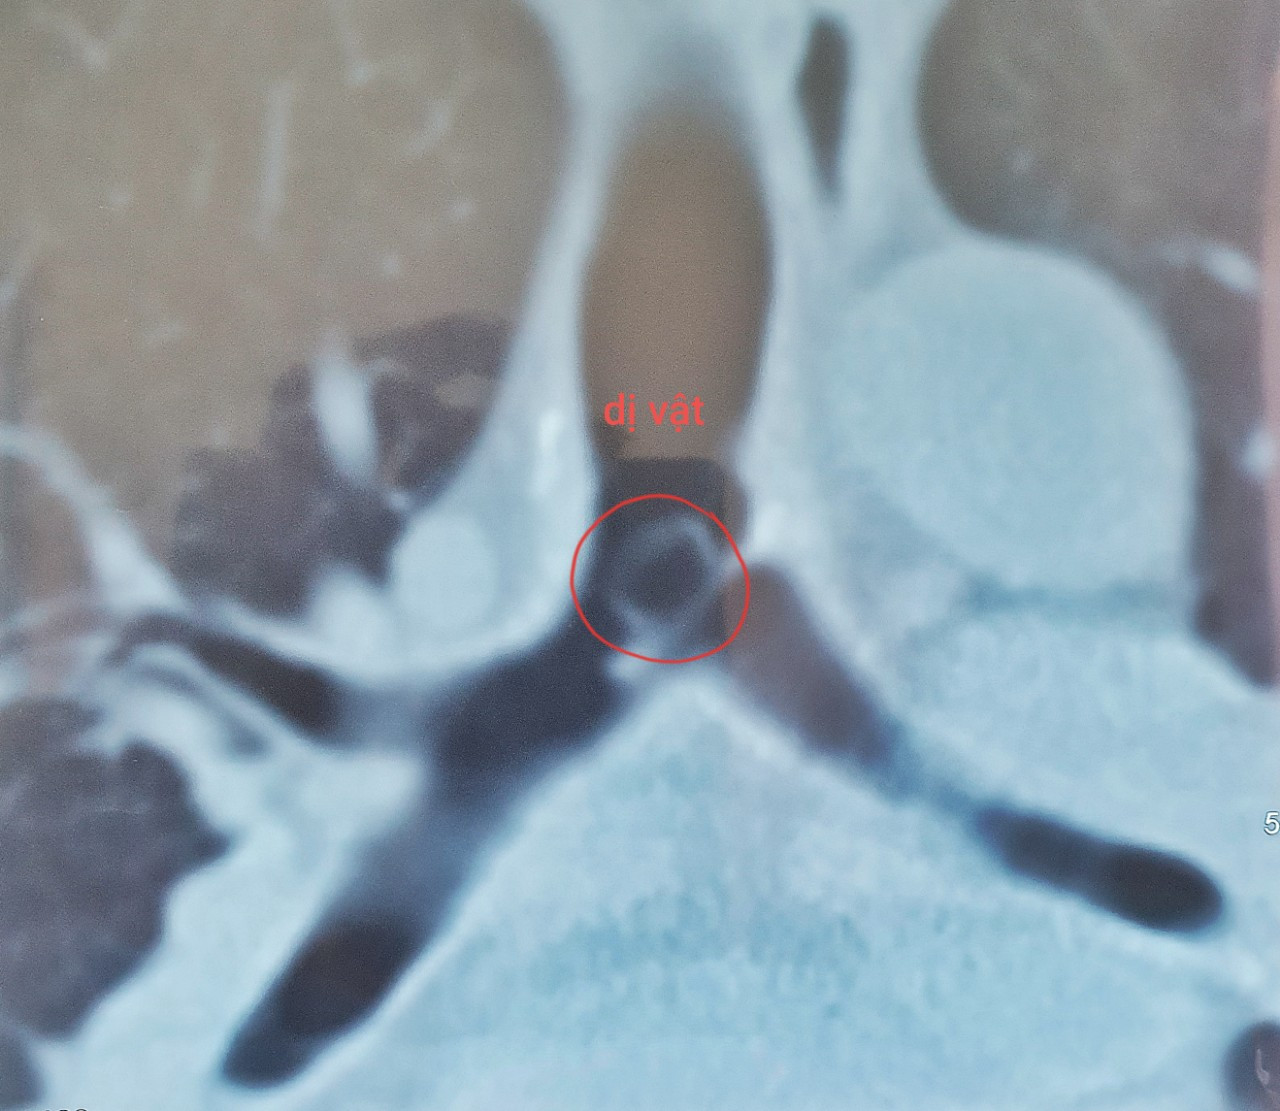

Dị vật nằm trong khí quản của ông T. Sau khi nhập viện, các bác sĩ đã tiến hành thăm khám và thực hiện các cận lâm sàng. Kết quả chụp CT scan lồng ngực phát hiện, ông T. có dị vật nằm trong khí quản.

Quá trình thực hiện, các bác sĩ phát hiện, có dị vật nằm ở khí quản che gần hết phế quản gốc trái bao phủ bởi đàm nhầy, hình thành mô hạt xung quanh dị vật.